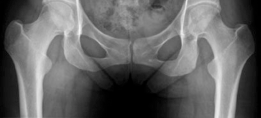

Radiographic and Advanced Imaging

Standard preoperative imaging must include an anteroposterior (AP) pelvis, cross-table lateral, and false-profile view of the affected hip. These evaluate for dysplasia, impingement morphology (cam/pincer), and degenerative changes.

Magnetic Resonance Arthrography (MRA) is the gold standard for evaluating the capsuloligamentous complex. Extravasation of contrast anteriorly often delineates the size and location of the capsular defect. MRA also assesses labral integrity, chondral damage, and the viability of the femoral head. A 3D computed tomography (CT) scan is highly recommended to quantify femoral anteversion and acetabular version, as unrecognized osseous malorientation (e.g., severe femoral retroversion) will predispose the reconstruction to failure if not addressed concurrently with a derotational osteotomy.